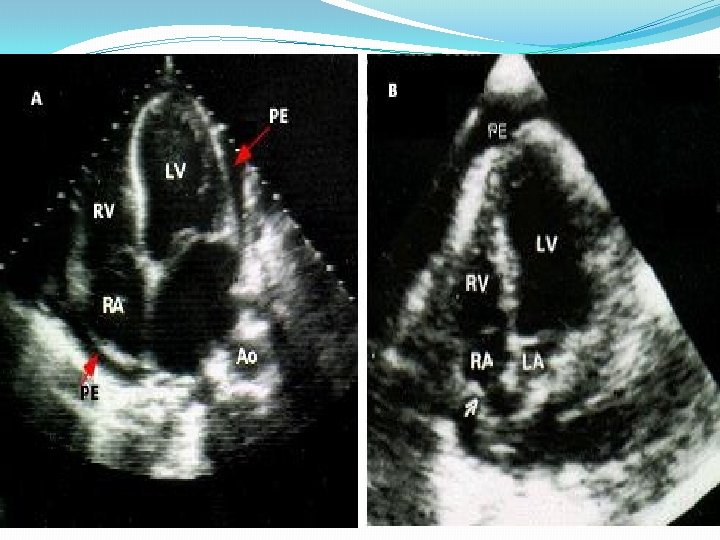

Echocardiogram The echocardiogram is often normal in patients with the clinical syndrome of acute pericarditis unless it is associated with a pericardial effusion. While the finding of a pericardial effusion in a patient with known or suspected pericarditis supports the diagnosis, the absence of a pericardial effusion or other echocardiographic abnormalities does not exclude it.

Echocardiography should be performed in all cases, and should be considered on an urgent basis if tamponade is suspected. Even a small effusion can be helpful in confirming the diagnosis of pericarditis, although the absence of an effusion does not exclude the diagnosis. In addition, echocardiography can be particularly helpful if purulent pericarditis is suspected, if there is concern about myocarditis, or if there is chest x-ray evidence of cardiac enlargement, particularly if this is a new finding.